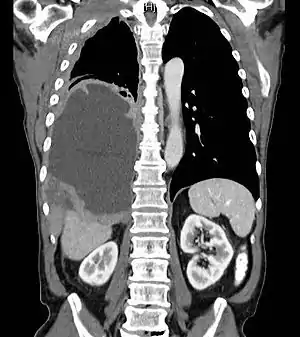

O diagnóstico pode ser suspeitado com um raio-x de tórax e uma tomografia computadorizada, sendo confirmado através de uma biópsia (amostra de tecido) e exame microscópica. Pesquisas sobre exames de rastreamento para detecção precoce do mesotelioma estão em andamento.